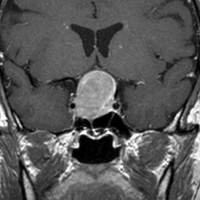

典型的なMRIの画像です

下垂体腺腫のMRIです。両側の視野障害(両耳側半盲)のために手術を受けた患者さんのものです。この腫瘍は非機能性腺腫といってホルモンを出さない腫瘍でした。少し大きめでしたが全部取れて視野の障害はよくなりました。

左の2枚はガドリニウム造影剤を使って写したもので腫瘍の形がよくわかります。右の1枚はT2強調画像と言います。MRIでは撮影の仕方によって見え方が違います。